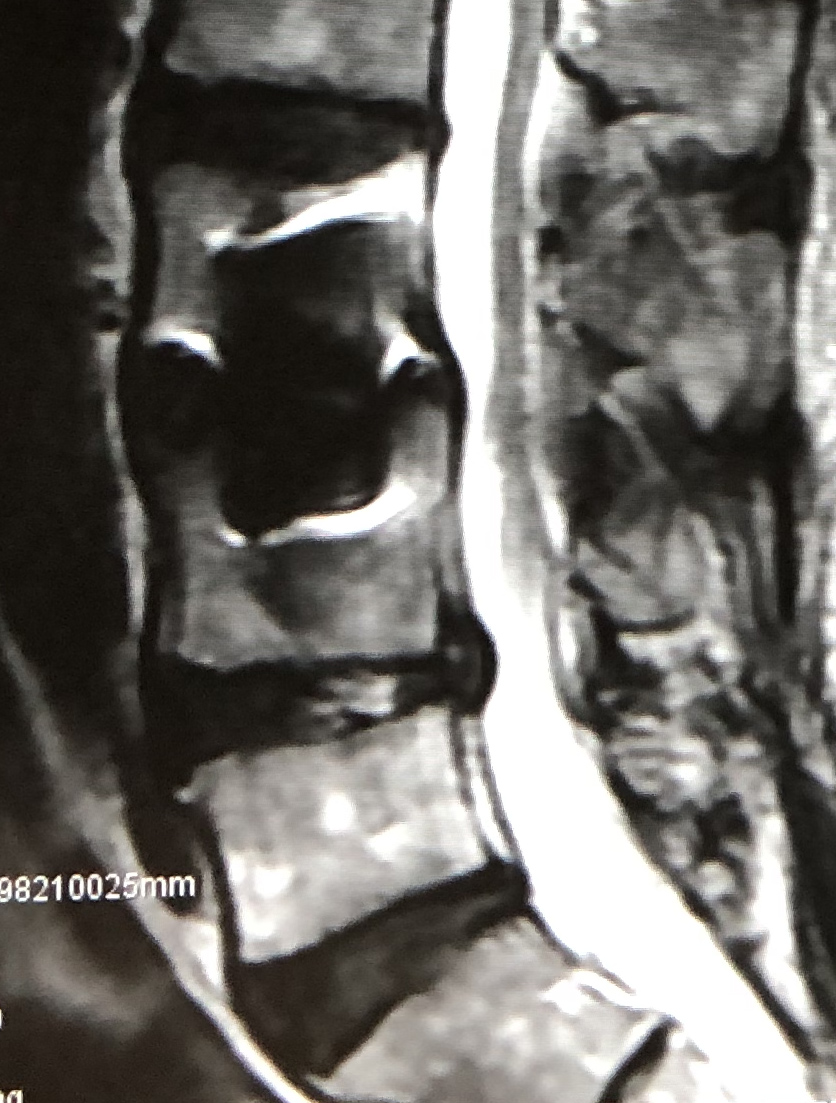

| MRI |

|